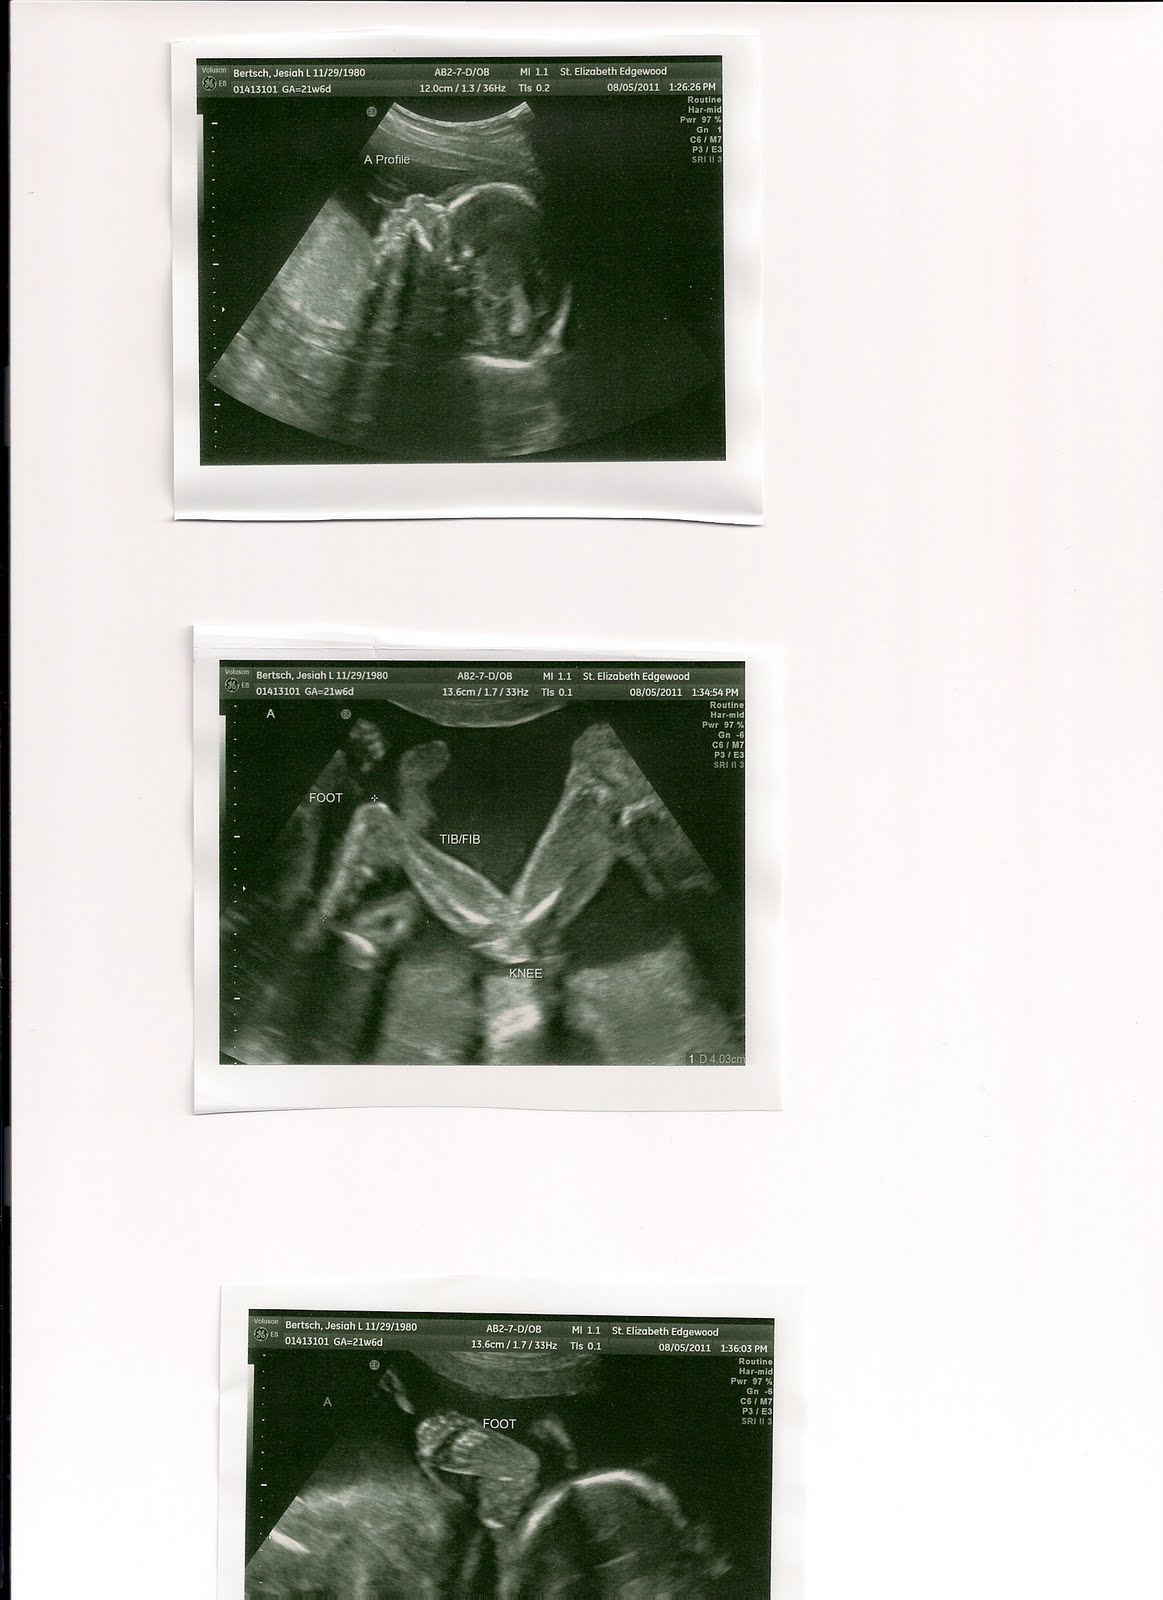

Today was really an exciting day. We had our anatomy ultrasound where the ultrasound is looking at each babies organs and growth to be sure there are no obvious abnormalities. As I laid on the table, I just kept praying that they would all be okay. It just doesn't seem possible that there could be no abnormalities seen with any of them. My prayers were answered as each baby was looked at very carefully and no abnormalities were found. Even baby boy C's kidney size had gone back to normal! They are growing well and beginning to beat up on each other in there! Several times we saw one of their feet come into view while looking at another baby only to witness the one being kicked by his brother or sister!

Her are the beautiful photos of our little ones. If only you could tell what to name them by the pictures... we are really struggling with names!

Baby A- Boy 1 lb 1oz

Baby B, Girl 1 lb